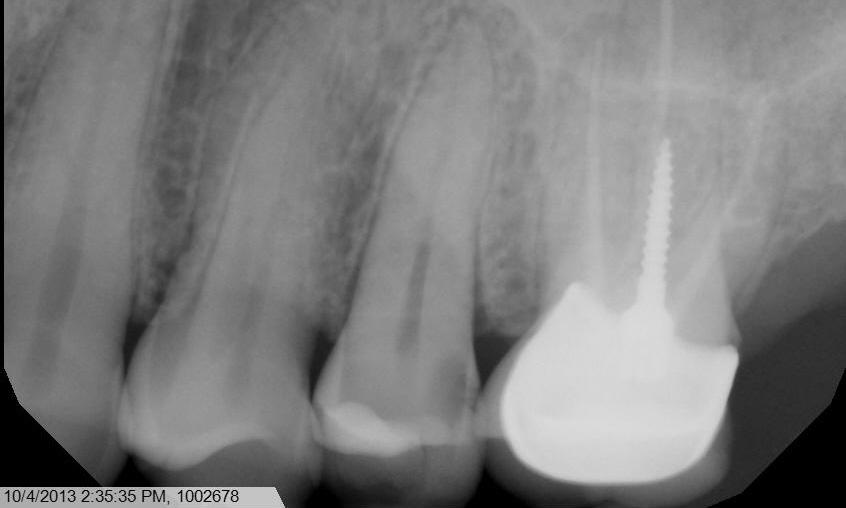

Root canal treatment. With the system we use, warm vertical fill of gutta percha is able to fill in lateral, or accessory, canal, which is difficult to achieve with traditional root canal treatment method.